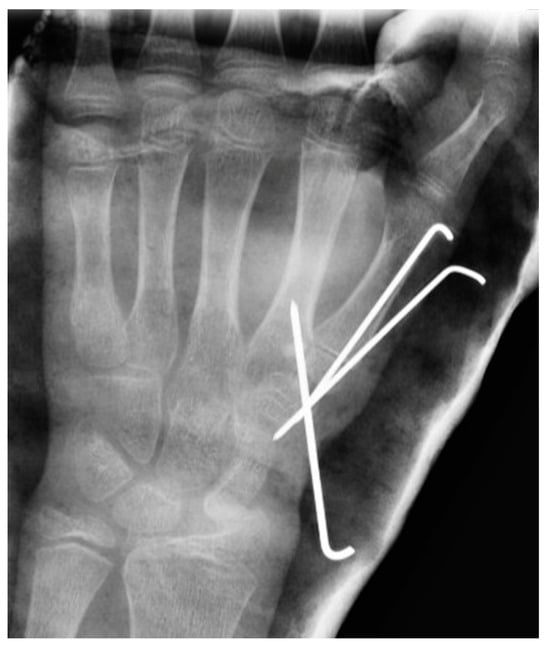

| 4 *** | 12 | M | Closed Reduction + KW Closed reduction and fixation with percutaneous K-wires | NO | X-ray shows favorable evolution (follow up at origin center) | NO | 0 |